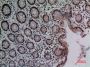

Applications WB, IF, IHC, ELISA

IF 1:50-200

WB 1:500-1:2000

IHC-P 1:100-300

ELISA 1:20000